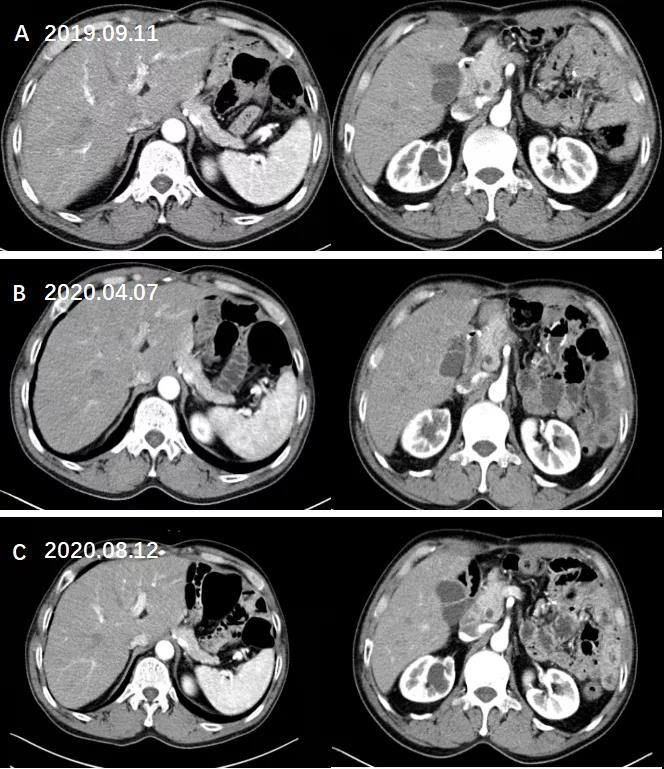

患者于2019.04.08~2020.08.10行20次卡培他滨 1.5g 口服 BID D1-D14+曲妥珠单抗治疗,3周方案。

于2020.09.06行1次曲妥珠单抗单药治疗,3周方案。

治疗后复查:未见复发迹象。

图11. 复查腹部CT增强未见复发迹象。